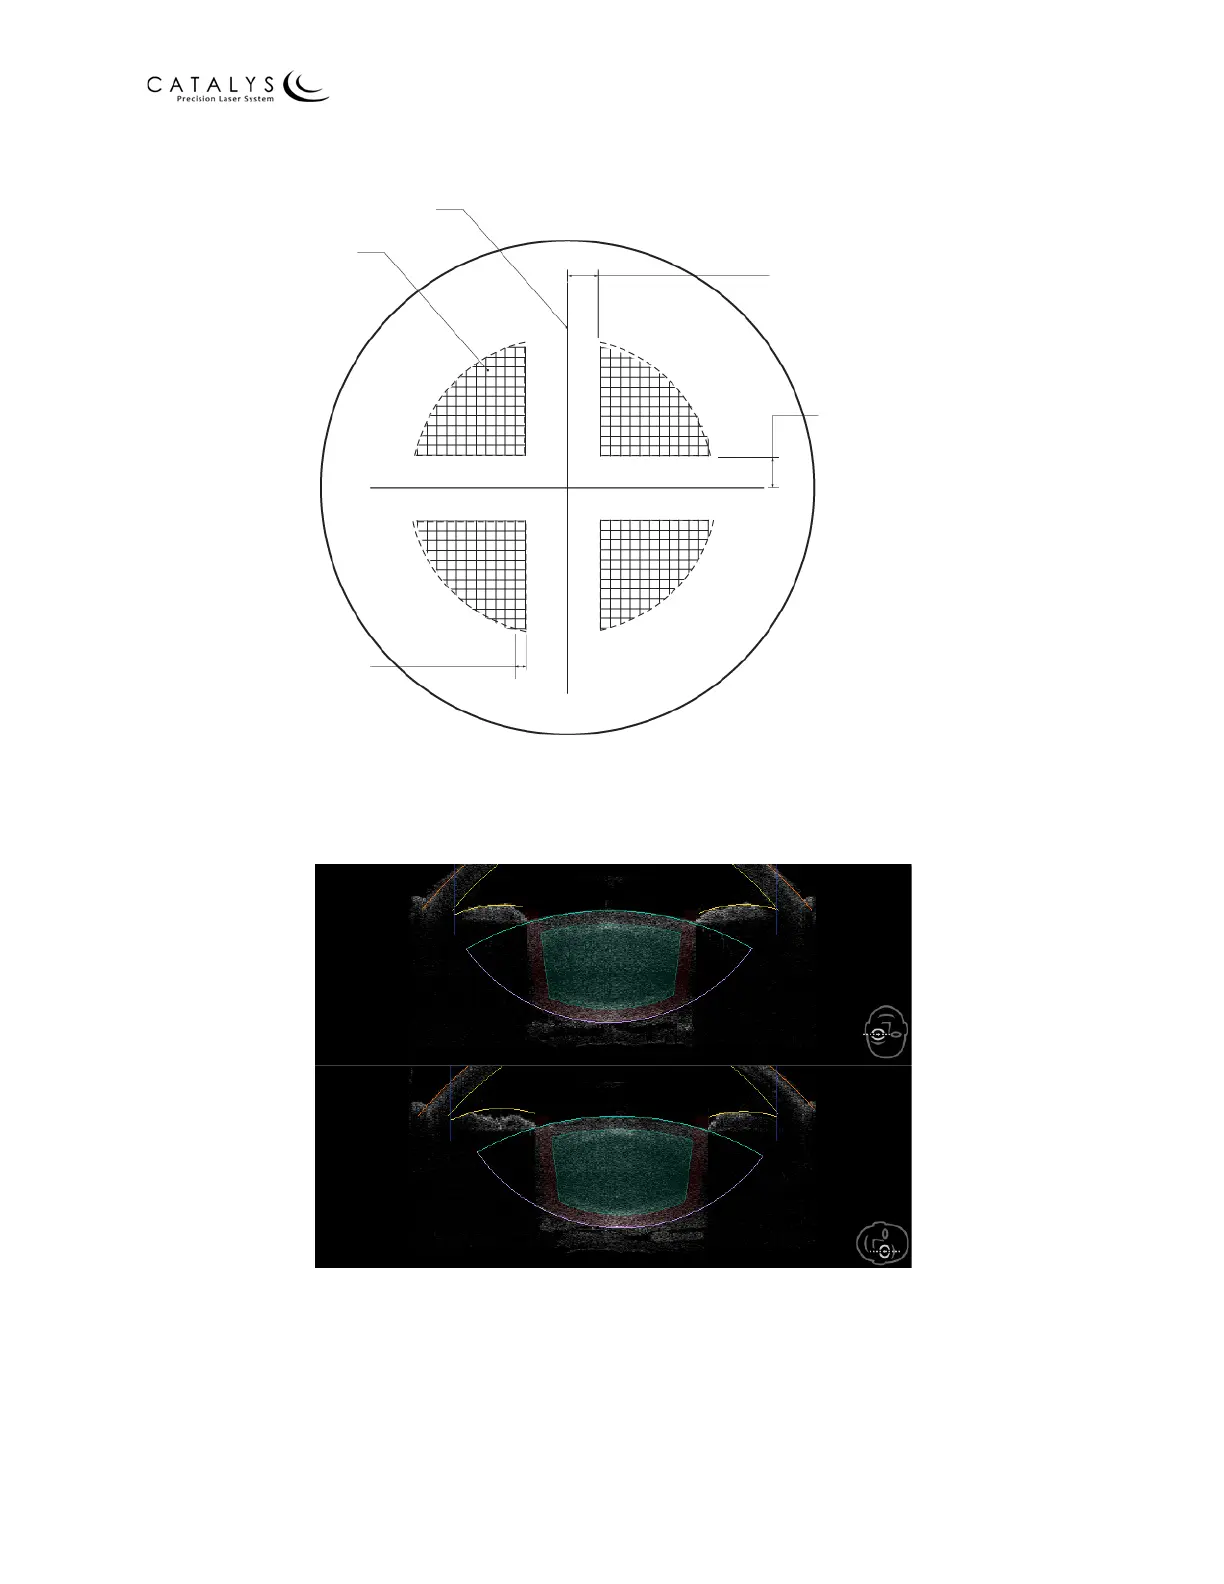

Figure 4.3 Lens Fragmentation Patterns

SEG/SOFT denotes distance between segmentation and softening. Incremental spacing is

available for each parameter, as shown.

Figure 4.4 Iris Safety Margins for Lens Fragmentation – Axial and Sagittal Views

Iris Safety Margin: axial (top) and sagittal (bottom) cross‐sectional views depict the slope of the

500 µm iris safety margin (shown in red) within the crystalline lens during lens fragmentation.

Segmentation

Softening

Grid Spacing

100 - 2000 µm

SEG/SOFT Spacing

100 - 1500 µm